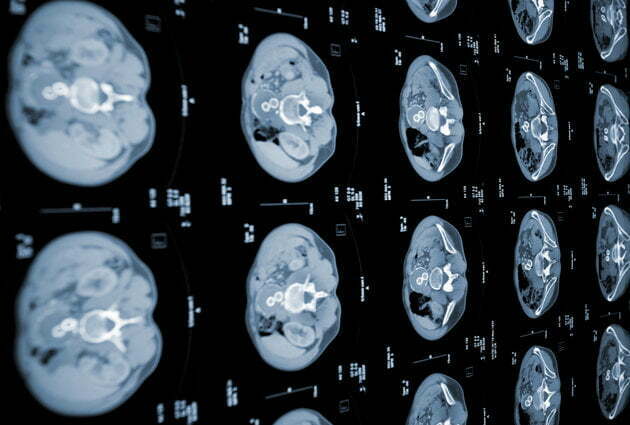

ظاهراً این محققین موفق به توسعهی نرم افزاری شدهاند که قادر است در کمتر از یک ثانیه سرطان روده را تشخیص دهد. بنا بر ادعای آنها طی آزمایشات صورت گرفته مشخص شده هوش مصنوعی این نرم افزار قادر است تومورهای خاصی موسوم به کلورکتال آدنوما (colorectal adenoma) که مستعد سرطانی شدن هستند را در عکسهای بزرگنمایی شدهی اندوسکوپی شناسایی کند.

از طریق فرآیند یادگیری ماشینی به این سیستم آموزش داده شده است که این عکسها را با 30000 تصویر دیگر مقایسه کند و بدین ترتیب در کسری از ثانیه وجود یا عدم وجود سلولهای سرطانی را در آنها تعیین نماید. نتایج و دستاوردهای این پروژه توسط دکتر «یوئیچی موری» محقق دانشگاه Showa در همایشی که حول بیماریهای دستگاه گوارش در شهر بارسلونا در حال برگزاریست تشریح شده است. به عقیدهی این دانشمند از طریق این روش ابداعی امکان شناسایی دقیق بیماری و برداشتن کامل پولیپهای سرطانی فراهم میشود و از انجام عملهای جراحی اضافه و غیرضروری اجتناب به عمل خواهد آمد. البته این امر در وهله اول مستلزم مورد پذیرش قرار گرفتن و تایید این شیوهی تشخیص بیماری توسط نهادهای قانونگذار است اما موری و همکارانش در این پروژه به آیندهی روشن آن بسیار امیدوارند.